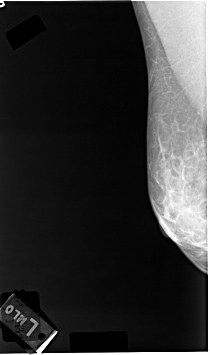

C_0039_1.LEFT_MLO

RIGHT_CC LINES 4712 PIXELS_PER_LINE 2680 BITS_PER_PIXEL 12 RESOLUTION 50 NON_OVERLAY

RIGHT_MLO LINES 4608 PIXELS_PER_LINE 2728 BITS_PER_PIXEL 12 RESOLUTION 50 NON_OVERLAY